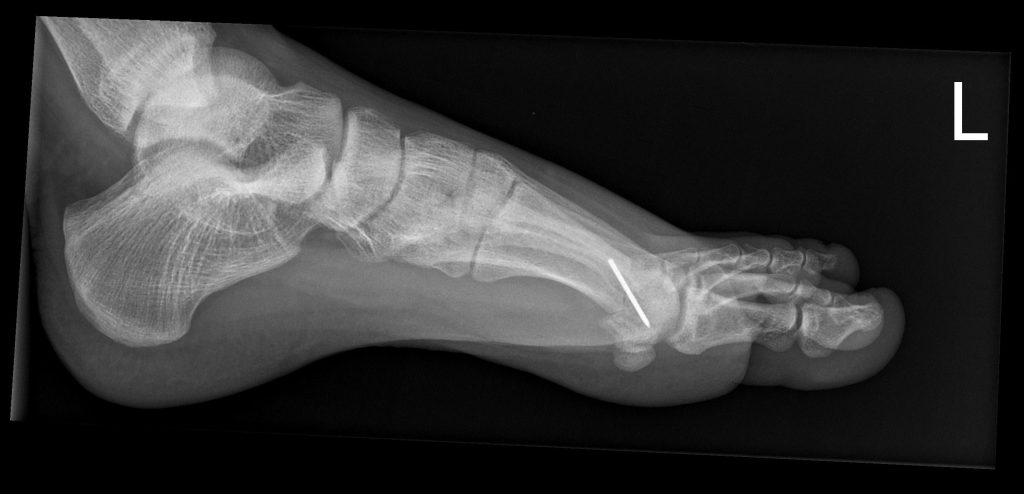

- Röntgen zur Beurteilung von Gelenkspalt, Osteophyten, Stellung

Youngswick Osteotomie

(Arthrose Gelenkspalt mehr als 50%, langer erster Mittelfußknochen)

Ist eine Modifikation der Chevron-Osteotomie ( OP bei Hallux valgus) dabei wird eine V- Förmige gelenknahe Durchtrennung des ersten Mittelfußknochens durchgeführt . ( in Kombination mit einer Cheilotomie) und eine Knochenscheibe entnommen, dadurch kommt es zu einer Verkürzung des ersten Strahls und einer Druckentlastung des Gelenks, was einer Verbesseerung der Beweglichkeit und Reduzierung der Schmerzen führt. Diese Operation führen wir häufig bei noch erhalten Gelenkspalt als Alternative zur Versteifung durch.